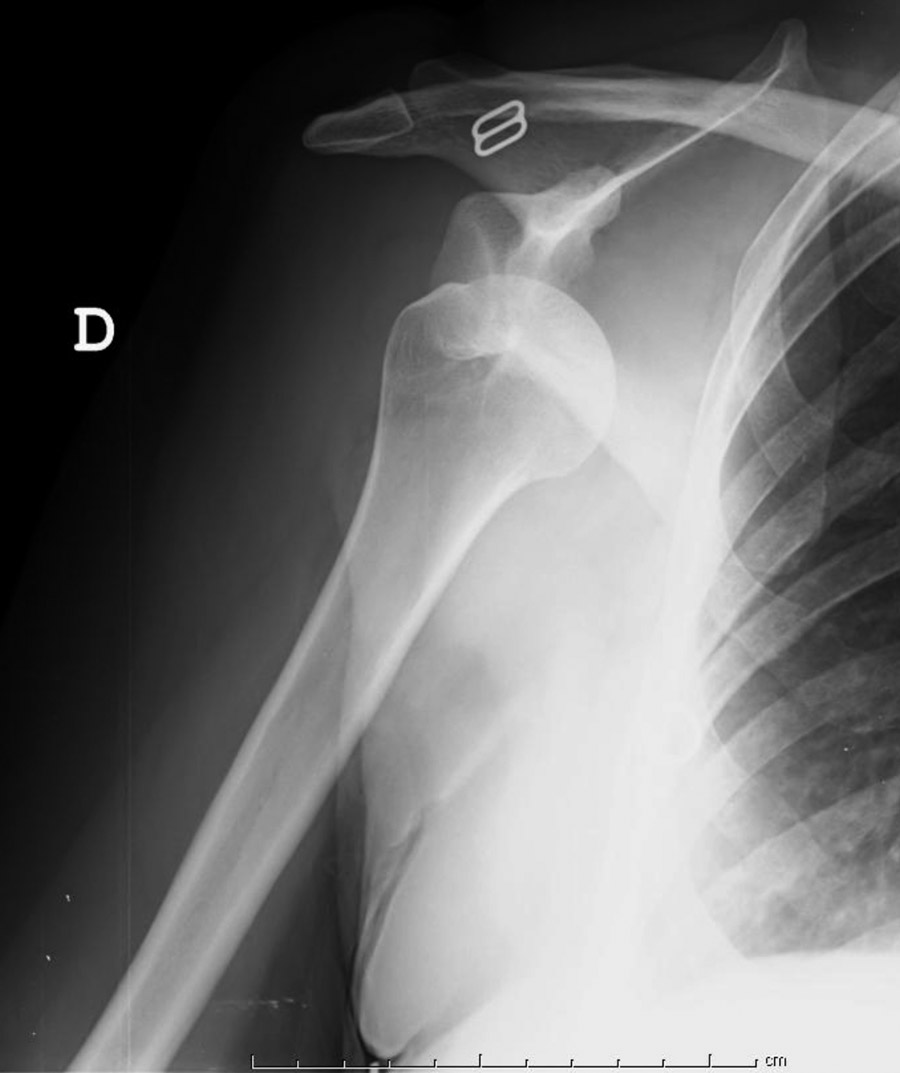

Las proyecciones más utilizadas son la anteroposterior (AP) de escápula, la axial de escápula (o en “Y”), la transtorácica y la axilar. La proyección AP verdadera de hombro (en el plano de la escápula) permite apreciar el descenso habitual de la cabeza y la incongruencia articular. Tras la reducción puede mostrar una fractura en la parte inferior de la cavidad glenoidea, que no se aprecie en proyecciones AP en el plano del tórax (Figura 2). En la proyección lateral o en “Y” escapular el contorno de la escápula se proyecta en forma de Y; en un hombro normal, la cabeza humeral queda dentro de la fosa glenoidea (Figura 3). La proyección transtorácica se realiza con el brazo contralateral levantado sobre la cabeza y se obtiene una imagen lateral en la que se puede observar la relación glenohumeral. La proyección axilar se realiza con el brazo en abducción de 15°; el haz del rayo pasa a través de la axila y permite apreciar la relación de la cabeza humeral con la glena.

Figura 2. Radiografía simple. Proyección anteroposterior de hombro en el plano del tórax. Se observa una luxación glenohumeral anterior.